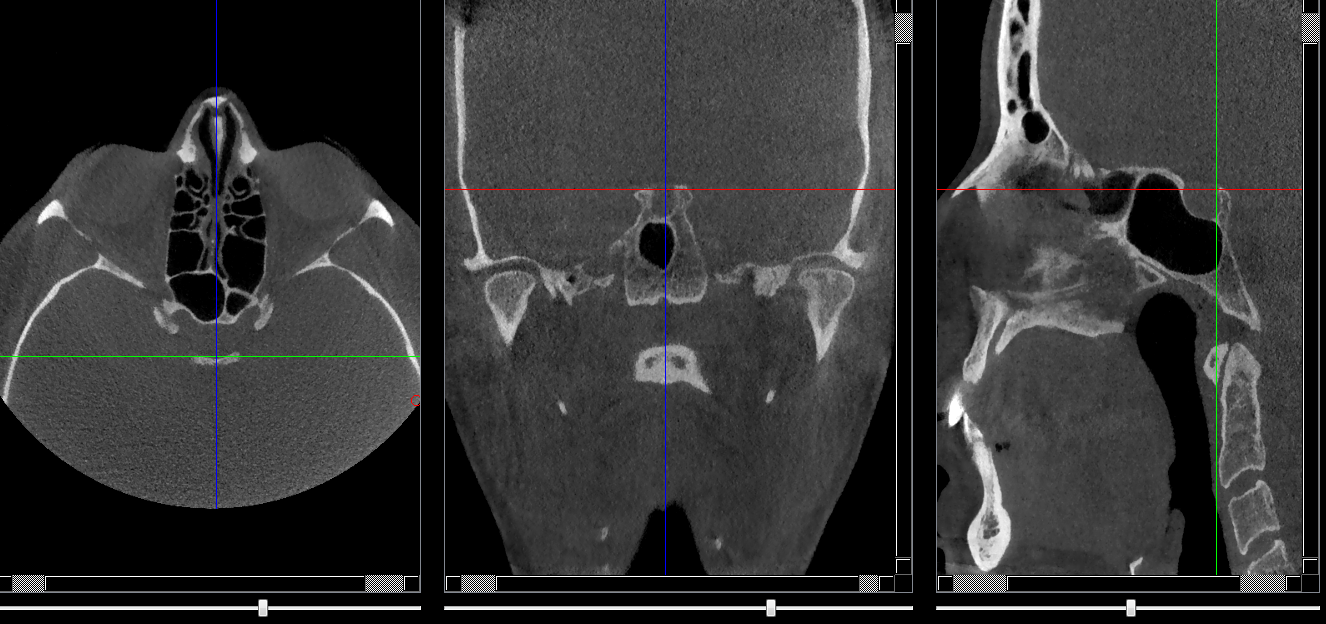

Selle turcique

Repères anatomiques

- Coupe transversale

- Début : Sinus sphénoide

- Fin : Processus clinoide

- Coupe frontale

- Début : Processus clinoide ant

- Fin : Processus clinoide post

- Coupe saggitale

- Début : Processus clinoide droit

- Fin : Processus clinoide gauche